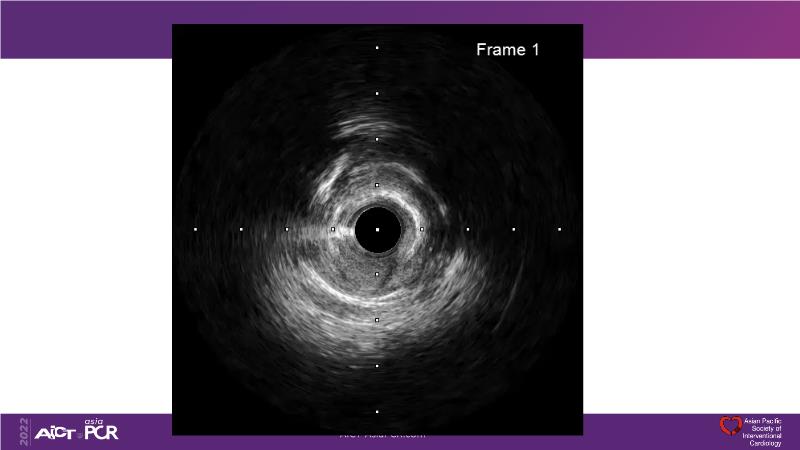

Cracking calcium: best practices to integrate intravascular lithotripsy into your calcium management algorithm

With this session, keep up to date on the evidence, trials and outcome data for intravascular lithotripsy in severely calcified lesions. Learn how to use this technique in real-world patients and understand its role in the treatment algorithm for severely calcified coronary lesions.